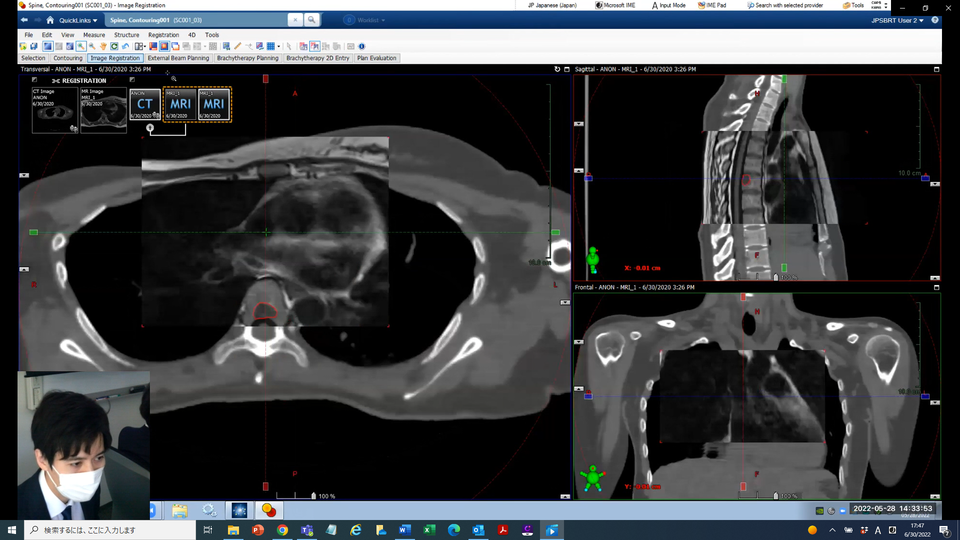

本ワークショップは本邦で脊椎SBRTを普及させるべく開催されました。ワークショップでは、臨床現場で必要な知識を習得するために、治療計画装置 (Eclipse) を用いたティスッションメインの実習形式で実施しました。